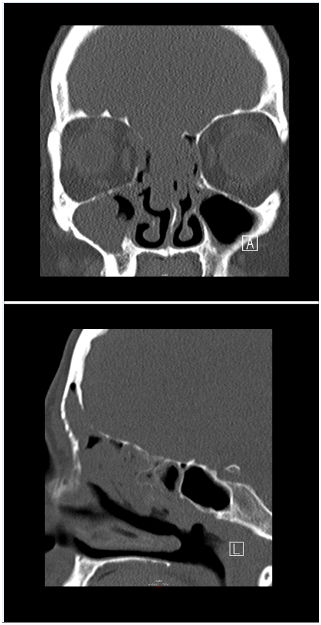

A 52-year-old Caucasian female with complaints of chronic nasal obstruction and anosmia was conservative treated for 2years. The patient was sent to our tertiary care center after developing a forehead swelling and decreased visual acuity. Contrast-enhanced CT-Scan and MRI (Figure 1 & 2) showed a large nasal cavity tumor, achieving both frontal sinuses, with bone expansion and erosion, and infiltrating the anterior cranial fossa. A nasal endoscopic guided biopsy was performed under general anesthesia and the histologic findings revealed a sinonasal undifferentiated carcinoma (SNUC). According to the current TNM classification of sinonasal tumors, the neoplasm was classified as cT4b. Further staging excluded cervical or distant metastases. This tumor was also classified as C, according to the Kadish System. After a promptly case presentation on our tumor board, and because an R0 resection would not be possible, a decision was made against a surgical treatment. A primary radiochemotherapy was recommended and initiated.

Figure 1 Contrast-enhanced CT-Scan showing a large nasal cavity tumor.